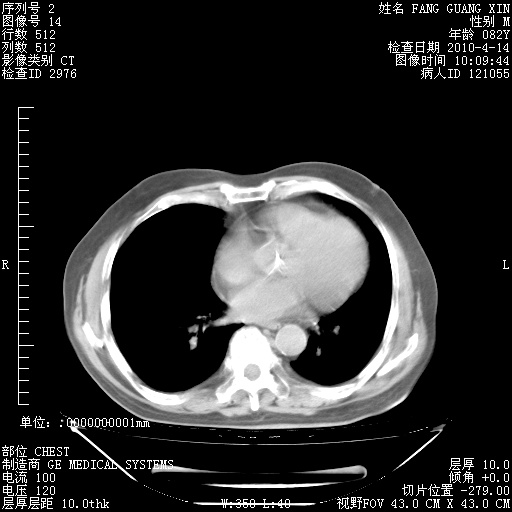

4月28日肺部CT——再次出现类似去年5月9日——透光度降低,(影像科认为)“间质性”改变。

4月28日肺部CT——再次出现类似去年5月9日——透光度降低,“间质性”改变。